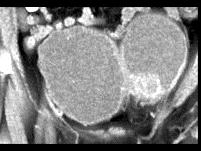

男,72岁,尿频,请根据所示图像作出最可能诊断 ( )A、膀胱癌B、输尿管癌C、先天性巨输尿管D、膀胱憩室E、输尿管囊肿

问题 男,72岁,尿频,请根据所示图像作出最可能诊断 ( )

选项 A、膀胱癌 B、输尿管癌 C、先天性巨输尿管 D、膀胱憩室 E、输尿管囊肿

答案 D